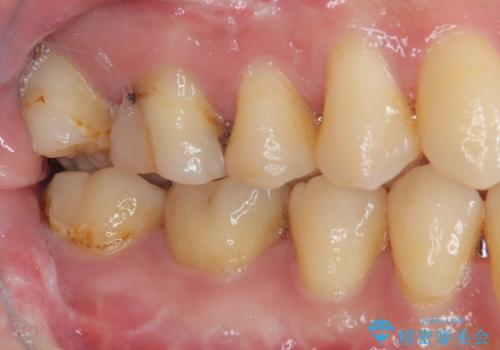

- 他院で矯正治療前後に処置を行った歯が痛むとのことで来院された患者様です。

下顎大臼歯は根管治療がされている歯が咬合時に痛みを感じ、上顎の大臼歯2歯は冷たいものがしみる状態でした。

まずはしみる上顎の歯を仮歯に置き換え、その後下顎の根管治療を行った上で、異常が認められなければオールセラミッククラウンにて補綴治療を行うこととしました。